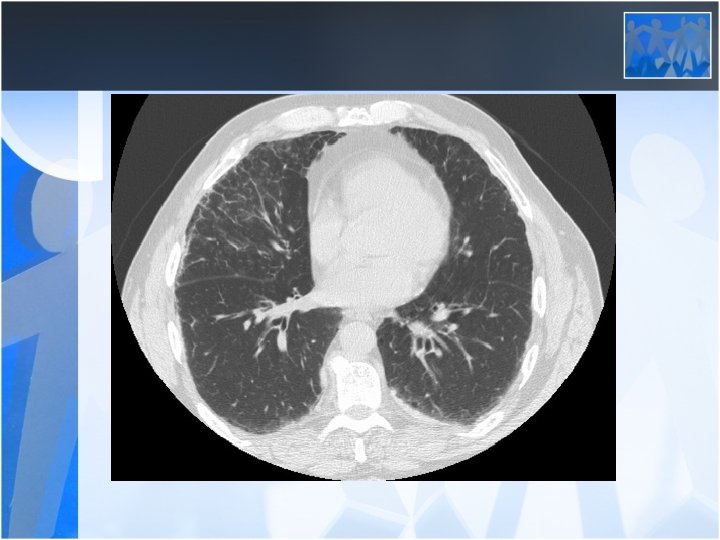

• Radiology is the most important diagnostic method for silicosis • Mainly upper and middle zone 3 -10 mm noduler opacities (silicotic nodules) • ILO clasification p, q, r • Hiler calcification (Egg shell calcification) PMF: • Coalescence of radiologic opacities (conglomeration • Nodules>10 mm • ILO clasification A, B, C • Honey combing can be seen in end stage disease